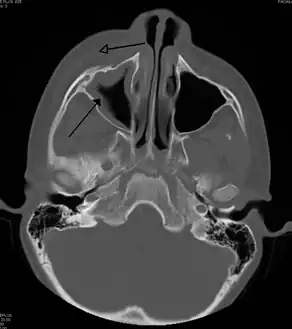

| Periorbital cellulitis caused by a dental infection (also causing maxillary sinusitis) | |

Periorbital cellulitis, or preseptal cellulitis, is an inflammation and infection of the eyelid and portions of skin around the eye anterior to the orbital septum.[1] It may be caused by breaks in the skin around the eye, and subsequent spread to the eyelid; infection of the sinuses around the nose (sinusitis); or from spread of an infection elsewhere through the blood.